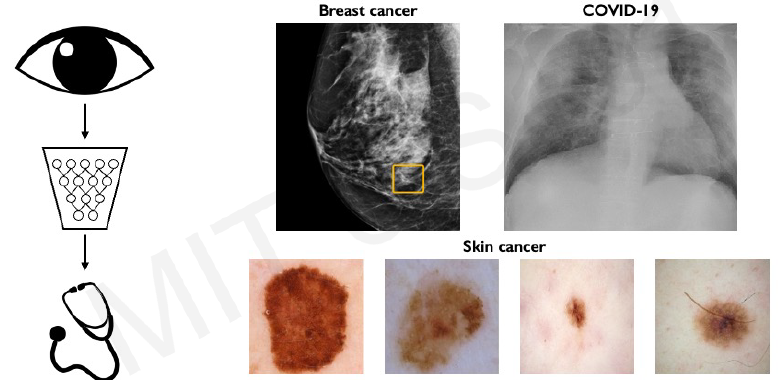

- Classification: Output variable takes class labels. E.g. Probability of belonging to a class